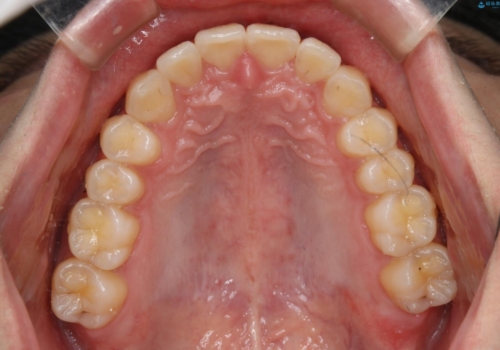

- 口元の突出感は気にならないが、上の前歯の角度と、下の前歯のがたつきが気になるとご相談にいらした方です。なるべく費用や治療期間を抑えて治療したいとのご希望に合わせて治療を計画しました。

この患者様への治療方針として、奥歯から少しずつ歯を移動させる方法と、歯をわずかに削って並べる方法とをご提案しました。短期間での治療を望まれたため、歯をサイズダウンさせて歯を並べました。わずかではあるものの、削った歯は元には戻せないことを十分ご説明し、ご理解ご了承を頂いた上で治療を行いました。